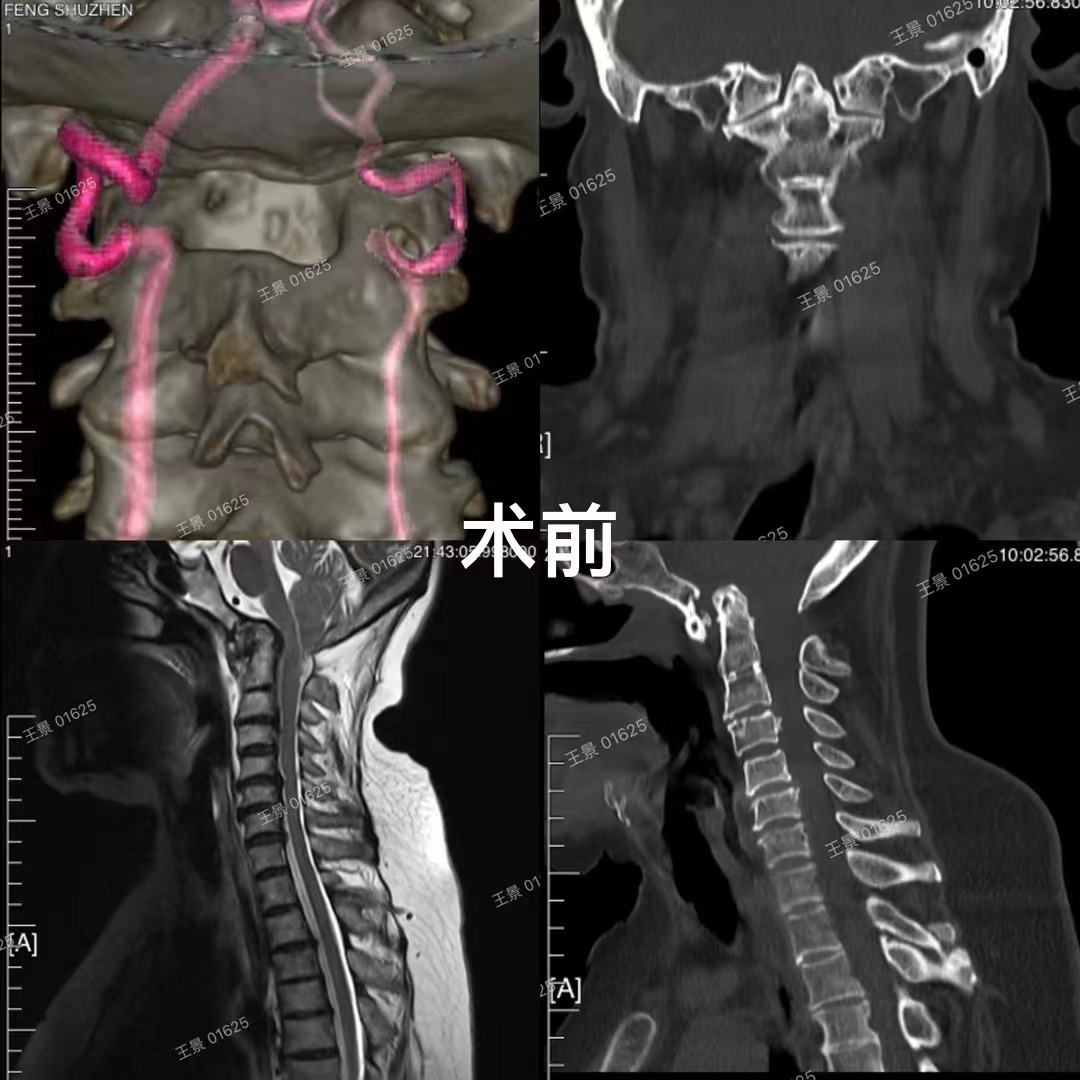

兰大二院骨科成功实施省内首例难复性寰枢椎脱位的后路松解椎间隙撑开复位融合手术

近日,兰大二院骨科二病区副主任医师王景团队采用后路松解椎间隙撑开复位融合技术,成功治疗多例复杂难复性寰枢椎脱位患者,经过数月随访,均取得满意疗效。

寰枢椎即第一、二颈椎,位于颅颈交界区,解剖结构复杂,毗邻延髓、椎动脉,且常常产生变异,手术难度和风险极高。寰枢椎脱位是由于多种病因使得寰枢关节失去正常对合关系,造成寰枢椎畸形脱位,脊髓压迫。引起颈不适、活动受限、四肢麻木无力、瘫痪以及吞咽困难等症状。严重者压迫呼吸循环中枢进而危及生命,全国仅少数大型三甲医院可开展寰枢椎脱位的矫形手术。

兰大二院骨科王景团队在既往治疗难复性寰枢椎脱位及颅底凹陷的经验和基础上,已完成多例显微镜辅助下难复性寰枢椎脱位的后路松解、椎间隙撑开复位融合技术,均取得良好效果。这项新技术在不需要外在牵引的情况下,使大部分难复性寰枢椎脱位得到了快捷安全有效的治疗,寰枢椎关节间融合也为颅颈交界区畸形手术提供了强有力支撑和有效融合界面。